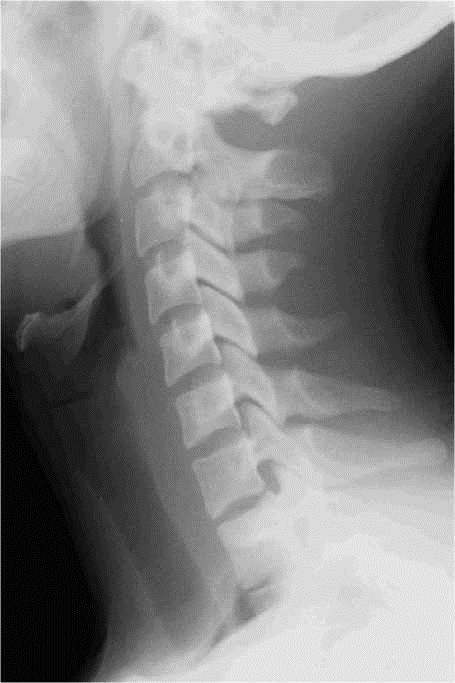

IMAGE NORMALE

PROFIL

– – Le patient est assis ou debout

– – En profil droit ou gauche

– – La tête est en légère déflexion

– – Le plan sagittal médian du crane est dans le prolongement du crane

– – Les épaules sont tombantes

– – La cassette déborde au dessous des épaules

RAYON DIRECTEUR

– – Il est centré sur C4 (milieu de la ligne passant par le maxillaire inférieur et l’épaule)

CRITERES DE REUSSITE

– – On doit voir de C1 à C7

– – On doit voir les parties molles

– – Le bord postérieur des corps doit être superposé, donc non dédoublé